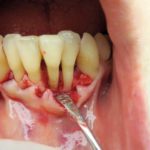

Perio-build-up: una tecnica di recupero con moderni biomateriali di denti con compromissione parodontale...

La tecnica presentata utilizza per la rigenerazione parodontale una membrana di derivazione ossea suina di tipo riassorbibile, utile per le sue caratteristiche di “relativa”...